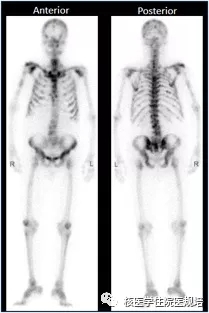

胸椎骨巨细胞瘤-PETCT检查案例